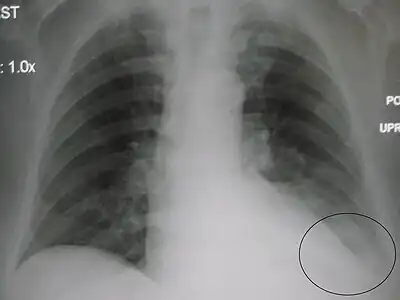

![]() Chest X-ray of a 30-year-old healthy man, with the costodiaphragmatic recess label in red ellipse | |

Pleural effusions collect in the costodiaphragmatic recess when in standing position,[2] and present on plain X-rays as "blunting" of the costophrenic angle.

In anatomy, the costophrenic angles are the places where the diaphragm (-phrenic) meets the ribs (costo-).

Each costophrenic angle can normally be seen as on chest x-ray as a sharply-pointed, downward indentation (dark) between each hemi-diaphragm (white) and the adjacent chest wall (white). A small portion of each lung normally reaches into the costophrenic angle. The normal angle usually measures thirty degrees.

Pleural effusion

With pleural effusion, fluid often builds up in the costophrenic angle (due to gravity). This can push the lung upwards, resulting in "blunting" of the costophrenic angle. The posterior angle is the deepest. Obtuse angulation is sign of disease.

Chest x-ray is the first test done to confirm the presence of pleural fluid. The lateral upright chest x-ray should be examined when a pleural effusion is suspected. In an upright x-ray, 75 mL of fluid blunts the posterior costophrenic angle. Blunting of the lateral costophrenic angle usually requires about 175 mL but may take as much as 500 mL. Larger pleural effusions opacify portions of the hemithorax and may cause mediastinal shift; effusions > 4 L may cause complete opacification of the hemithorax and mediastinal shift to the contralateral side.